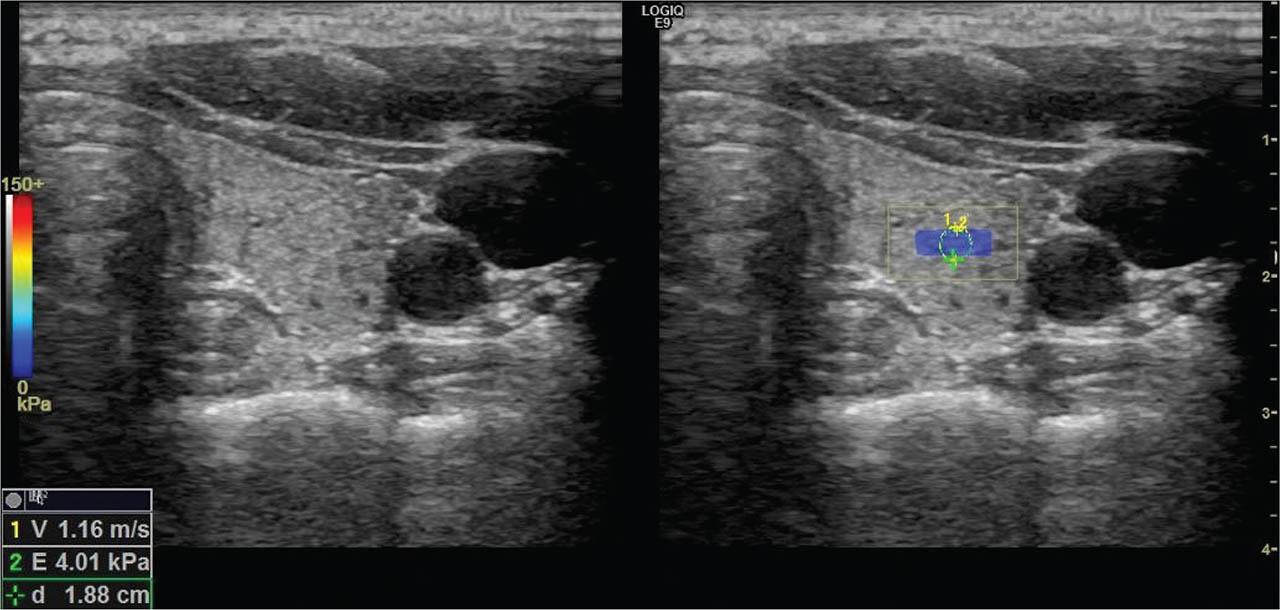

Figure 1